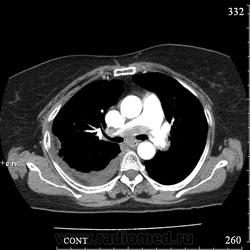

Еще один случай диагностики ТЭЛА методом КТ-ангиографии у женщины 59 лет. Основная клиническая жалоба - выраженная одышка. Определяется: полный дефект наполнения в системе правой ЛА (бифукация и нижнедолевая), неполный дефект наполнения в левой ЛА (нижнедолевая), пристеночные тромбы по задней стенке в области бифуркации обеих легочных артерий. Инфаркт (массивное кровоизлияние) нижней доли правого легкого. Правосторонний малый (120см3) гидроторакс. Несмотря на выраженные тромбы, поперечники легочных артерий - в пределах нормы.; на нативной (безконтрастной) КТ - тромбы не видны. Несмотря на почти полный дефект наполнения в левой нижнедолевой артерии, изменений в легочной ткани левого легкого нет. Также приводится топограмма, как вариант, приближенный к рутинной рентгенограмме